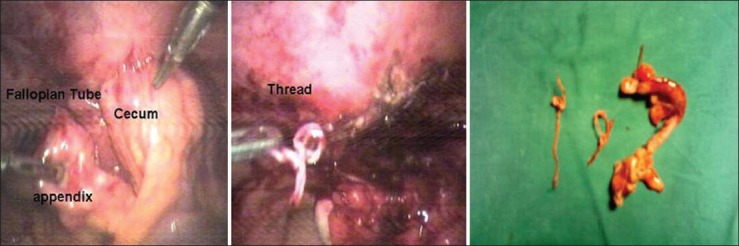

Tubo-ovarian abscess usually results from ascending infection of the lower genital tract. In few cases, it can occur as a result of direct contamination at the time of tubal sterilization. We describe two rare cases of “tubo-ovarian stitch abscess” after post-partum tubal sterilization and managed successfully by laparoscopy at a tertiary care teaching hospital.